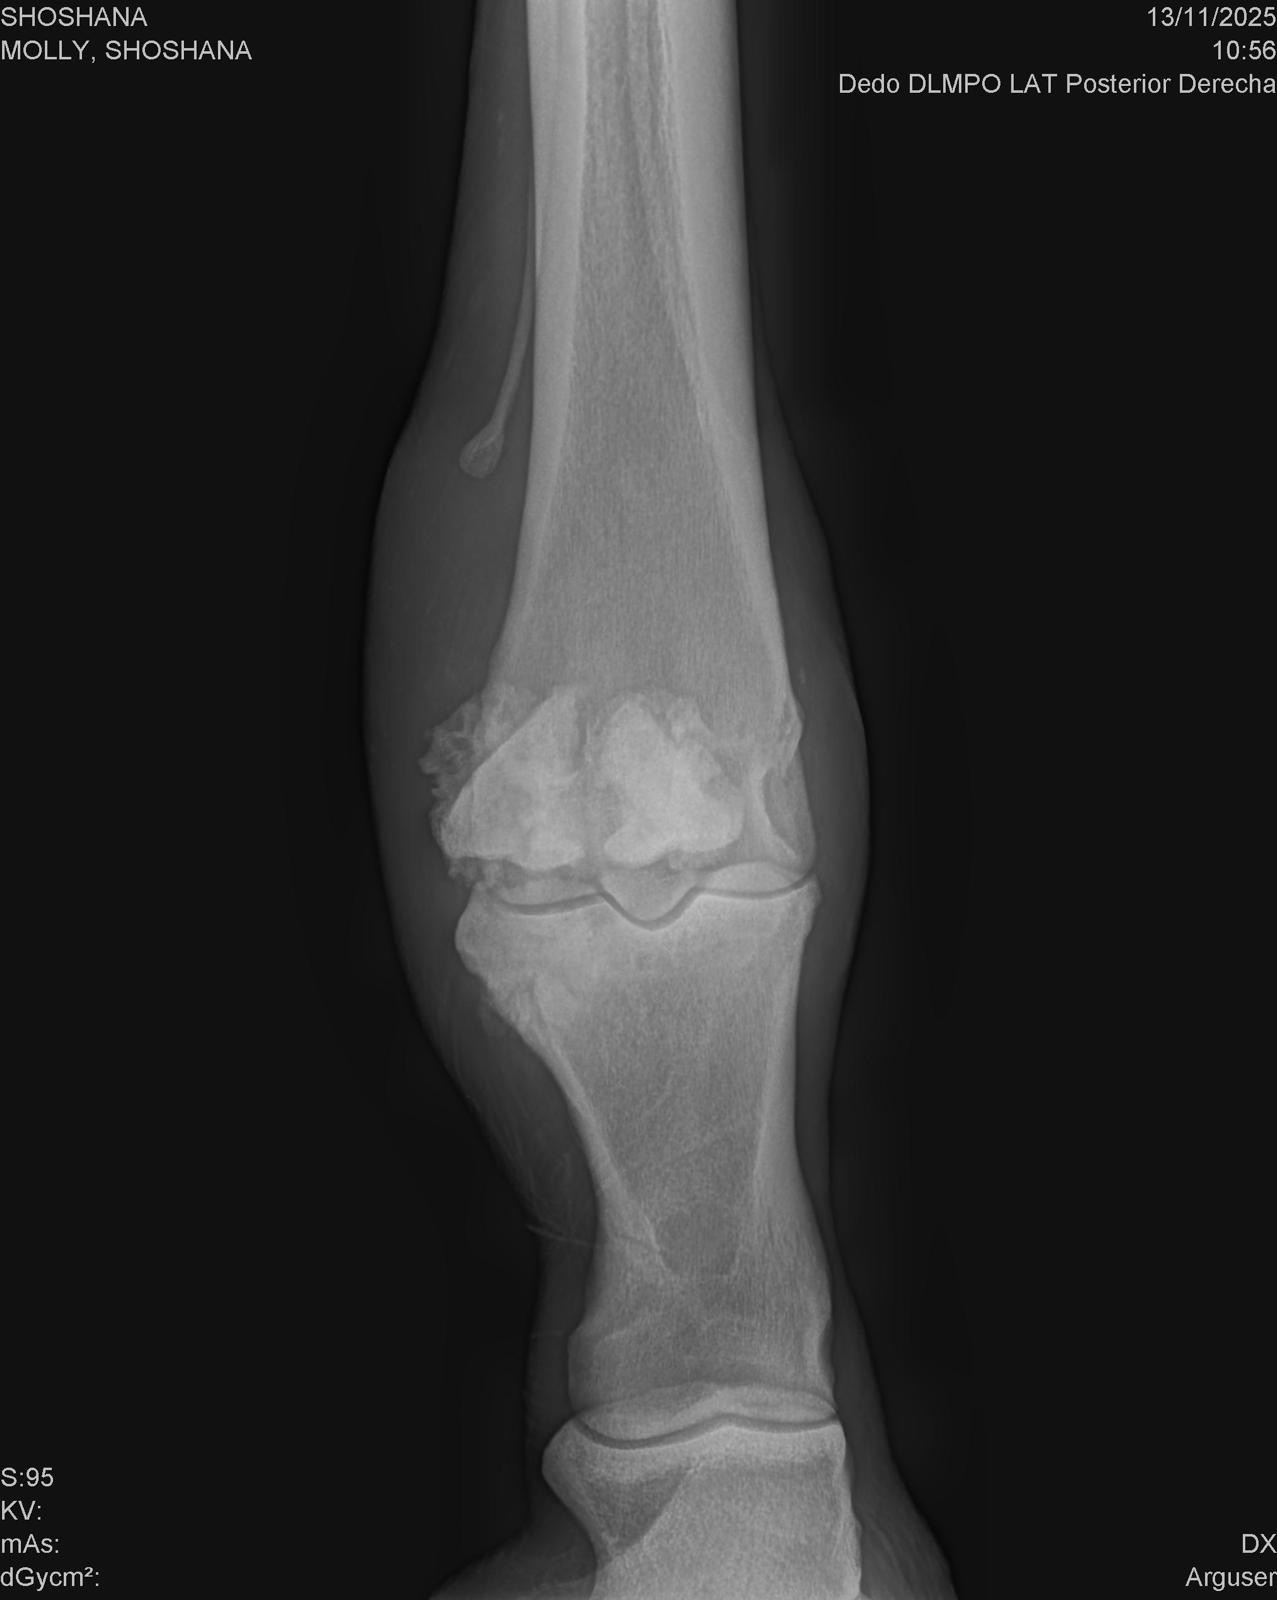

As she began her recovery, the reason for her abandonment slowly became clear. Shoshana has equine OCD (osteochondritis dissecans) — a serious yet treatable joint condition that has caused a piece of bone to fragment and float within her joint. This fragment has now caused a painful joint infection, putting her at significant medical risk.

Just a few days ago, Shoshana suffered a new and serious injury. While running in the field, she likely slipped, tearing the sesamoid ligaments at the back of her hock. This has caused the sesamoid bone to become displaced, adding severe pain and instability to an already fragile situation.

• Her OCD is chronic and will require surgery to resolve it

• The torn ligaments and displaced sesamoid bone also require surgical intervention

• Before any surgery can begin, they must flush the hock joint and treat the infection with aggressive antibiotics

• Her prognosis remains “reserved”, meaning she still has a fighting chance — but only with immediate and intensive care